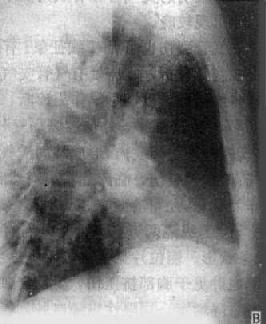

(1)一侧性肺不张:X线现为患侧肺野均匀致密,纵隔向患侧移位,肋间隙变窄(图3-1-7)。健侧肺可有代偿性肺气肿。

图3-1-7 一侧性肺不张

左侧支气管阻塞引起左侧全肺不张,显示左侧肺野均匀致密,

纵隔向患侧移位,肋间隙变窄,膈升高